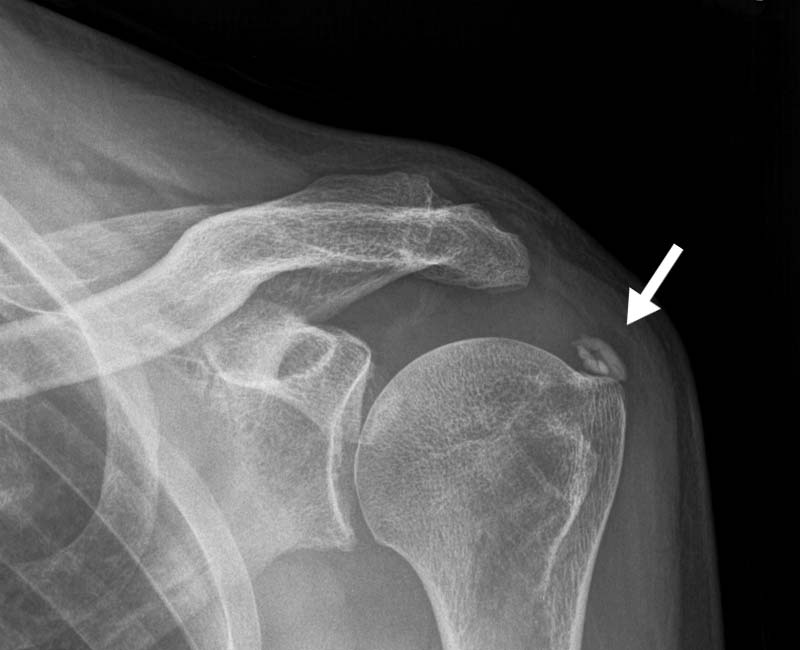

Xray of shoulder joint, calcification of tendon. Stock Image M110 Calcification Of Joints Shoulder Your healthcare provider may recommend rest and physical therapy. calcific tendinopathy (ct) of the shoulder is a common, painful condition identified by the existence of calcium deposits in the rotator cuff tendons. It usually results in shoulder pain with decreased range of motion. calcific tendinopathy is a disorder of the shoulder of unknown etiology. calcific tendonitis is. Calcification Of Joints Shoulder.